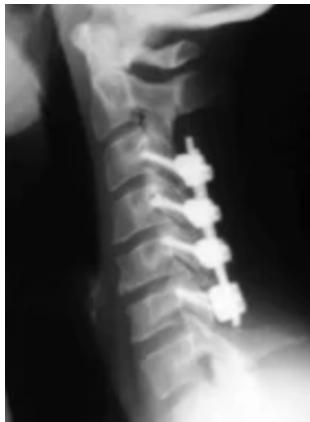

Imaging Examples:

Surgical Treatment - Anterior Cervical Discectomy and Fusion: